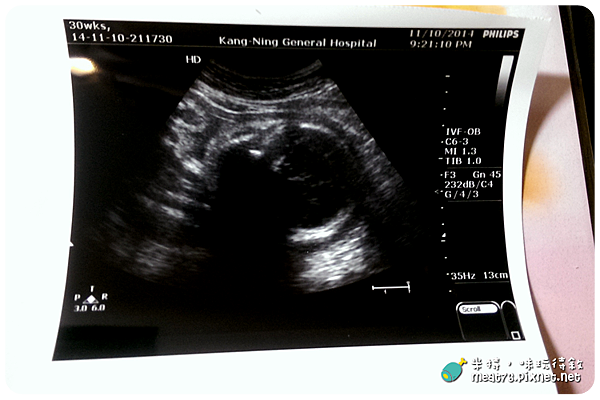

2014-11-10-1【孕婦產檢紀錄7】30W+1|康寧醫院|妊娠性糖尿病報告,抽血驗B肝(健保給付)

【懷孕產檢紀錄8】30W+1|康寧醫院|妊娠性糖尿病報告,抽血驗B肝 ( 健保給付 )